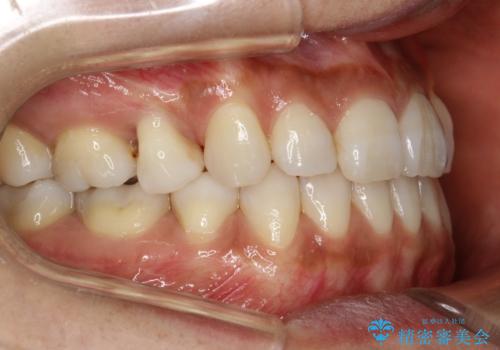

ハーフリンガル抜歯矯正 八重歯を改善する

- 小臼歯4本抜歯によるハーフリンガル・ワイヤー矯正を計画した。

シビアな八重歯がきれいに歯列にはいることにより、笑った時の印象などもかなり大きく変わります。